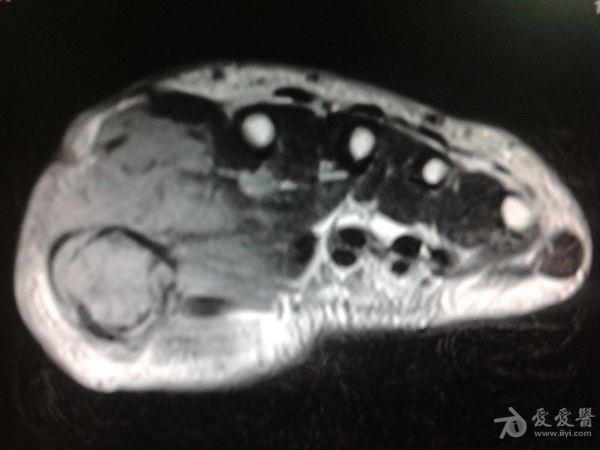

右第一掌骨、大多角骨肿瘤

男性患者,81岁,右手肿痛3个多月。无任何其它症状。体查:右手第一掌骨部肿胀明显,第一指活动受限,余四指活动可,腕关节活动小部分受限,活动时会痛。影像学检查如下。活检示:弥漫性大B细胞淋巴瘤。大家看看需不需要截肢?现在有人主张手术;有人主张不手术,直接化疗。大家有什么看法?